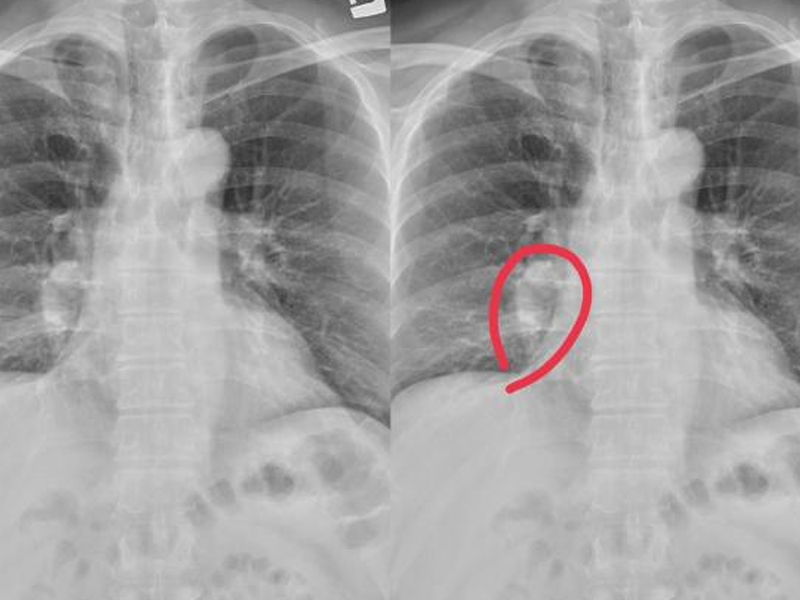

肺結節與惡性肺癌的關係:早發現早治療